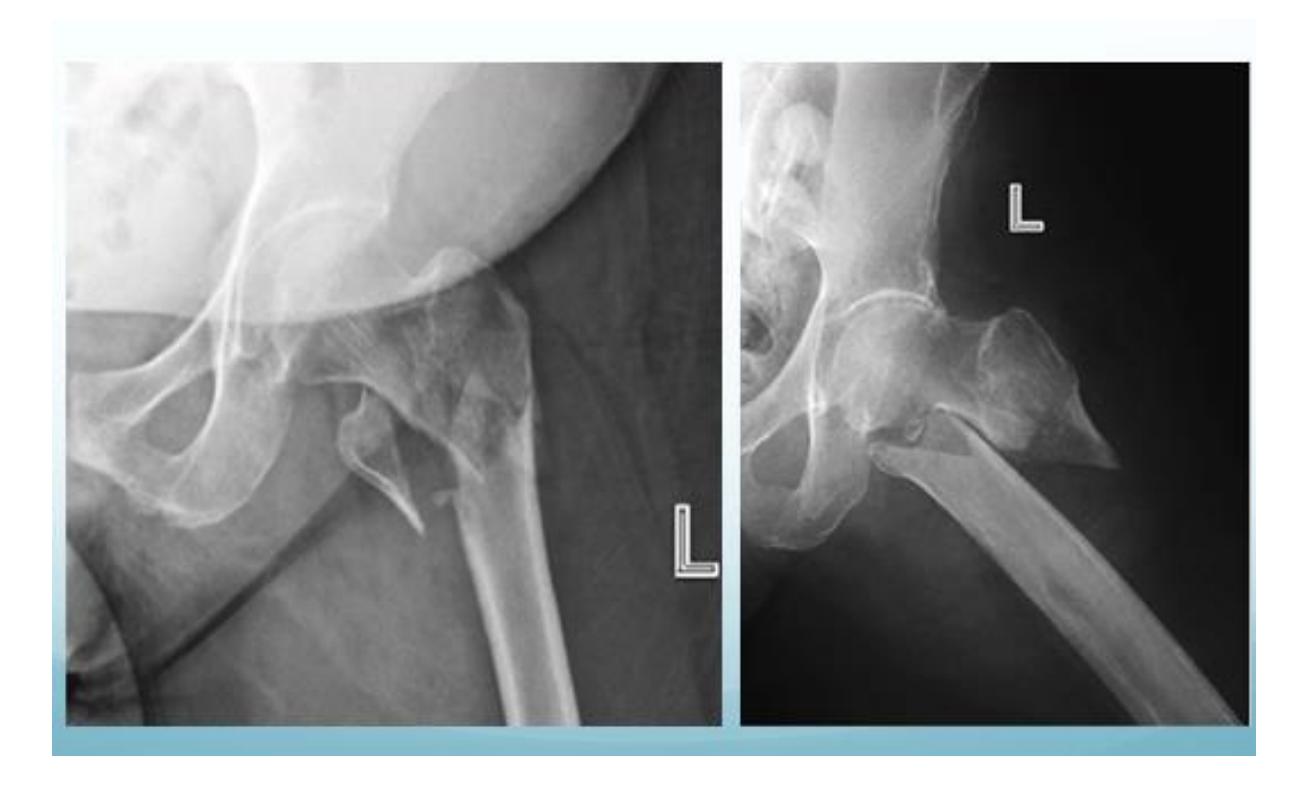

Intertrochanteric Fracture

Diagnosis: Intertrochanteric fracture of neck of femur Treatment: Dynamic hip screw or proximal femoral nail

Q8: 70-year-old female with hip injury

A 70-year-old inactive female presents to the emergency department after falling down in the bathroom. Sheโs been complaining from hip pain and inability to bear weight. Which of the following is the most appropriate choice of treatment?

- Bipolar hemiarthroplasty

Q22: 30-year-old active patient with femoral neck fracture

30-year-old active patient presents to ER after history of falling down from second floor. Diagnosed with displaced femoral neck - he has only mild controlled hypertension - what is the next step for his management?

- Anatomical reduction and cannulated screws